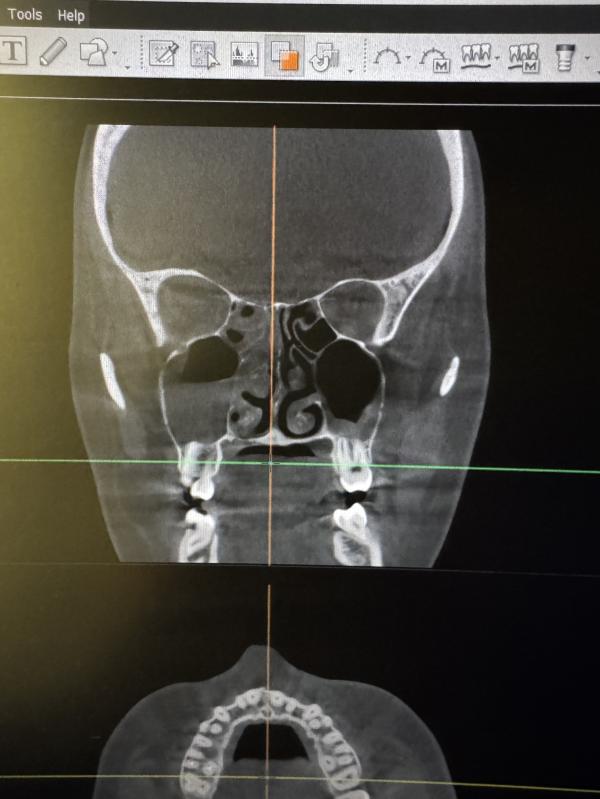

Всем привет , это же гайморит ?🫠к врачу только завтра

Да.С одной стороны уровень жидкости в гайморой пазухе и решетках воспаление-гайморит /этмоидит,с другой утолщение слизистой в гайморовой .

Похоже на то. Дай бог ограничиться консервативным лечением